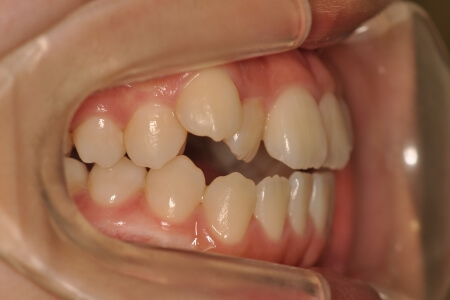

開咬(非抜歯)【2137】

初診時

年齢

15歳 性 別 女性

治療内容の詳細 初診時15歳の女性で、上の歯のがたつき、かみ合わせ、歯の中心のズレ、鼻から下が長いのを気にされ来院されました。

検査の結果、上顎前歯部叢生および開咬を伴うアングルⅠ級不正咬合と診断しました。